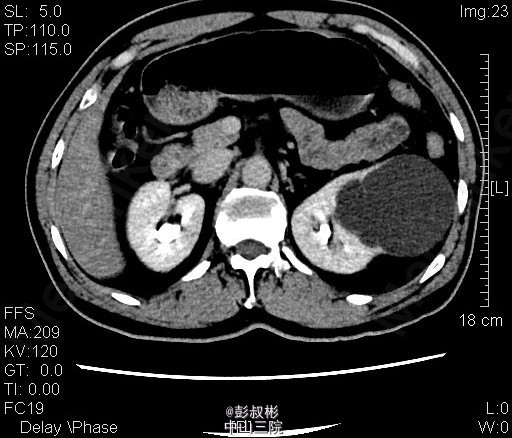

3、查体:腹稍膨隆,无压痛、反跳痛,未触及肿物,双肾区无红肿、隆起,无叩痛,双侧肋脊点、肋腰点无压痛。腹平软,双侧上中输尿管点无压痛,膀胱区无压痛。双侧腹股沟区未触及肿物。 4、CT:双肾多发囊肿,左肾囊肿较大,推压左侧肾盂肾盏。左肾小结石.轻度弥漫性脂肪肝

5、左肾囊肿 6、住院后完善相关检查,查血、尿常规,生化,凝血,心电图,胸片等未见明显异常。CT:双肾多发囊肿,左肾囊肿较大,推压左侧肾盂肾盏。左肾小结石.轻度弥漫性脂肪肝。经术前准备,行单孔腹腔镜下肾囊肿去顶术,手术顺利,术后予预防感染、营养支持等治疗,术后恢复较好,术后病理示:左肾囊肿。